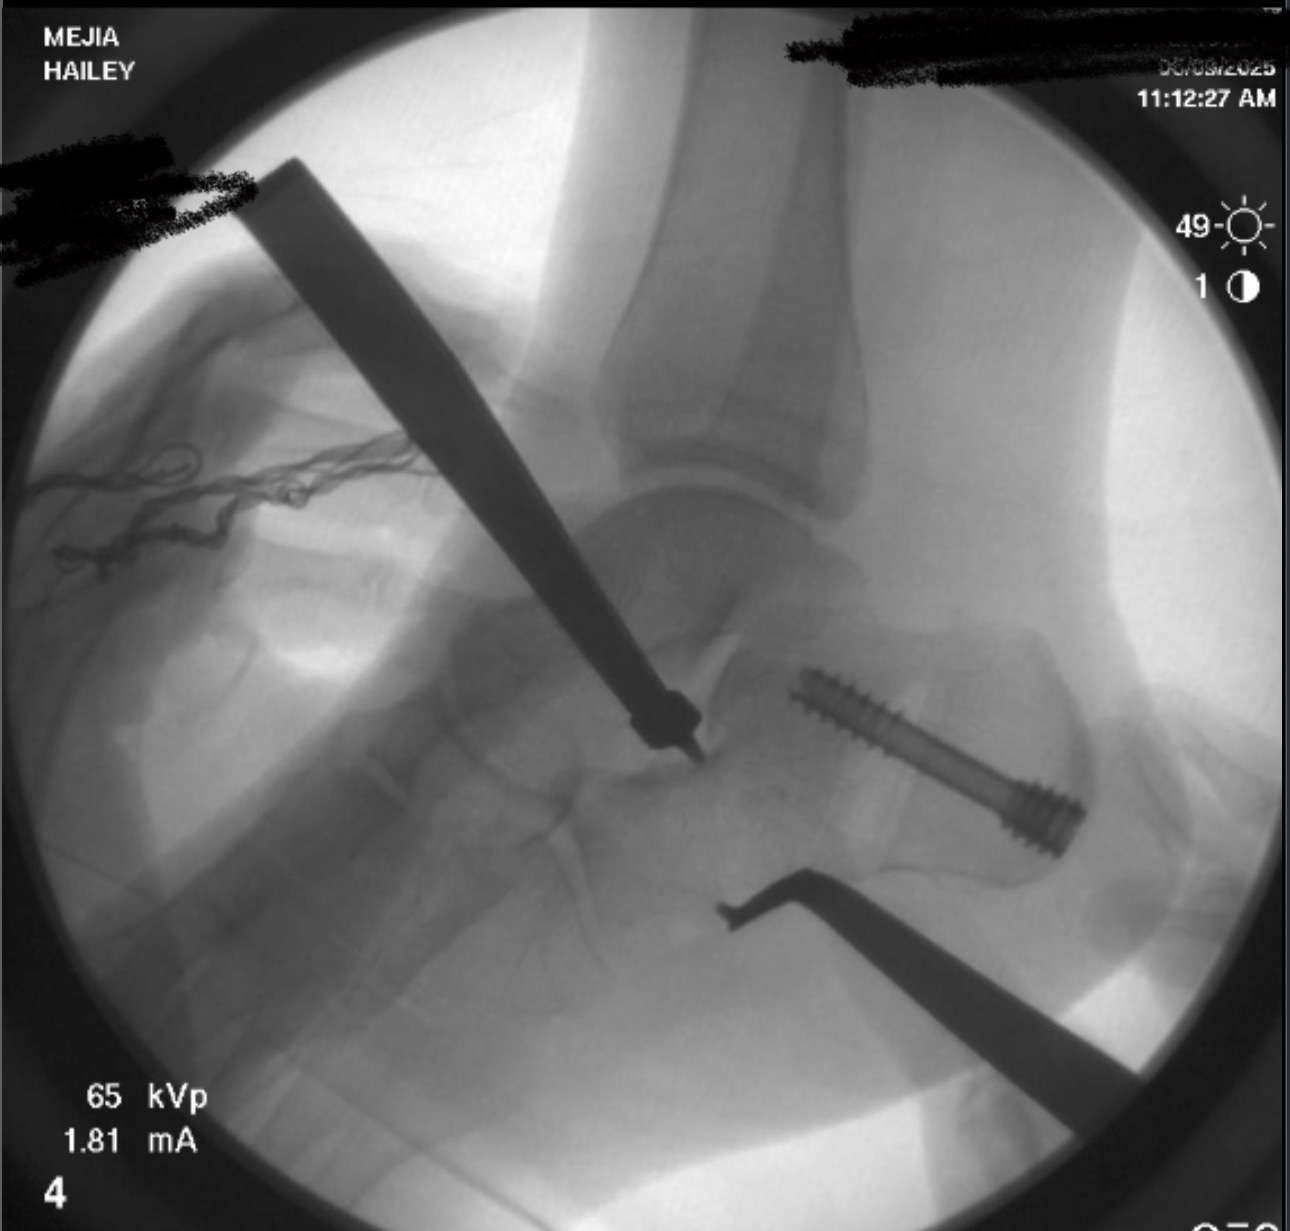

Hailey’s surgery went well, and we are incredibly thankful for all the love, prayers, and support we've received.

We are still facing a remaining balance due to an unexpected change from an outpatient to a hospital setting — a decision made solely by the medical team for Hailey’s safety. This balance also helps cover her upcoming physical therapy sessions as she begins the healing and recovery process.